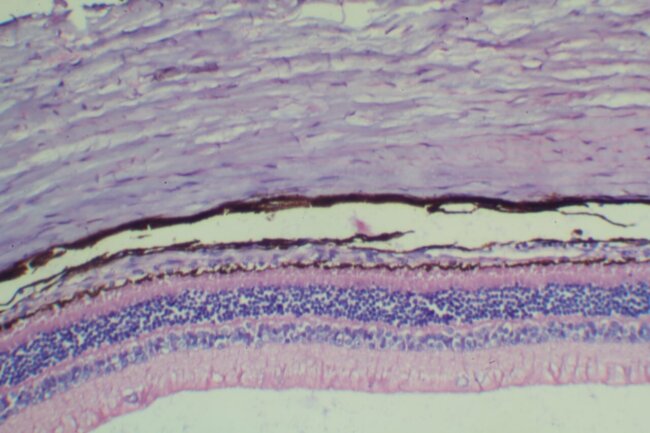

HE染色

By

立众小編1號

2021-07-01